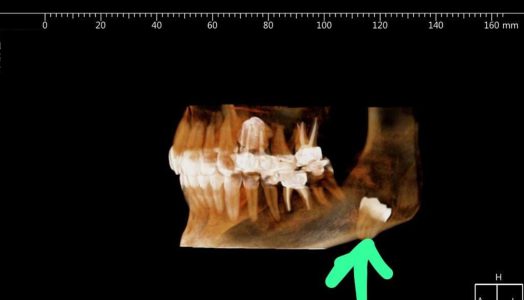

שירות חדשני לרופאי שיניים: CBCT + ייעוץ מומחה א.א.ג

[vc_row][vc_column][vc_custom_heading text="לאחר שזיהינו צורך מצד רופאי שיניים, לקבל שירות ייעוץ יעיל וממוקד ממומחי א.א.ג בסוגיות משותפות, החלטנו בקבוצת א.ר.ם להרים את הכפפה ולהקים שירות ייחודי, מקצועי ומהיר למטרה זו." font_container="tag:h2|text_align:right"][/vc_column][/vc_row][vc_row][vc_column][vc_column_text] מערך השירות החדש כולל: ייעוץ רופא א.א.ג מומחה באותו היום + CBCT במפתח רחב (במידת הצורך) וייעוץ בתחומים משיקים בהמשך, לפי הנדרש. Cone beam […]

CT נמוך קרינה, בממשק דנטלי

[vc_row][vc_column][vc_custom_heading text="שרות רדיולוגי חדשני – מענה רדיולוגי משופר בממשק רפואת פה ולסת – א.א.ג CT המאופיין ברמת קרינה נמוכה ביותר, המוערכת בכ 10% – 30% קרינה בלבד, בהשוואה למכשיר CT קונבנציונלי " font_container="tag:h2|text_align:right"][/vc_column][/vc_row][vc_row][vc_column][vc_column_text] הטכנולוגיה דגם PLANMECA ProMax 3D MID מאפשר שדה ראייה (Field Of View) של 17X20 ס"מ, הרחב בהרבה בהשוואה למכשירי ה CBCT הנפוצים, […]